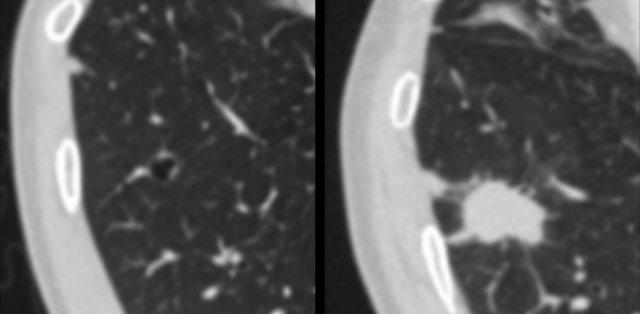

Ví dụ về ung thư phổi dạng nang với thành phần đặc hướng ngoại (bảng trái) và hướng nội (bảng phải).

- Thành phần đặc hướng ngoại hoặc hướng nội tiếp giáp với khoang khí dạng nang (hình).

Các hình ảnh minh họa thêm các ví dụ về ung thư phổi dạng nang với dày thành không đều mỏng (bảng trái) và dày (bảng giữa), cùng hình ảnh phức tạp hơn với kính mờ lan rộng và các khoang khí đa thùy (bảng phải).